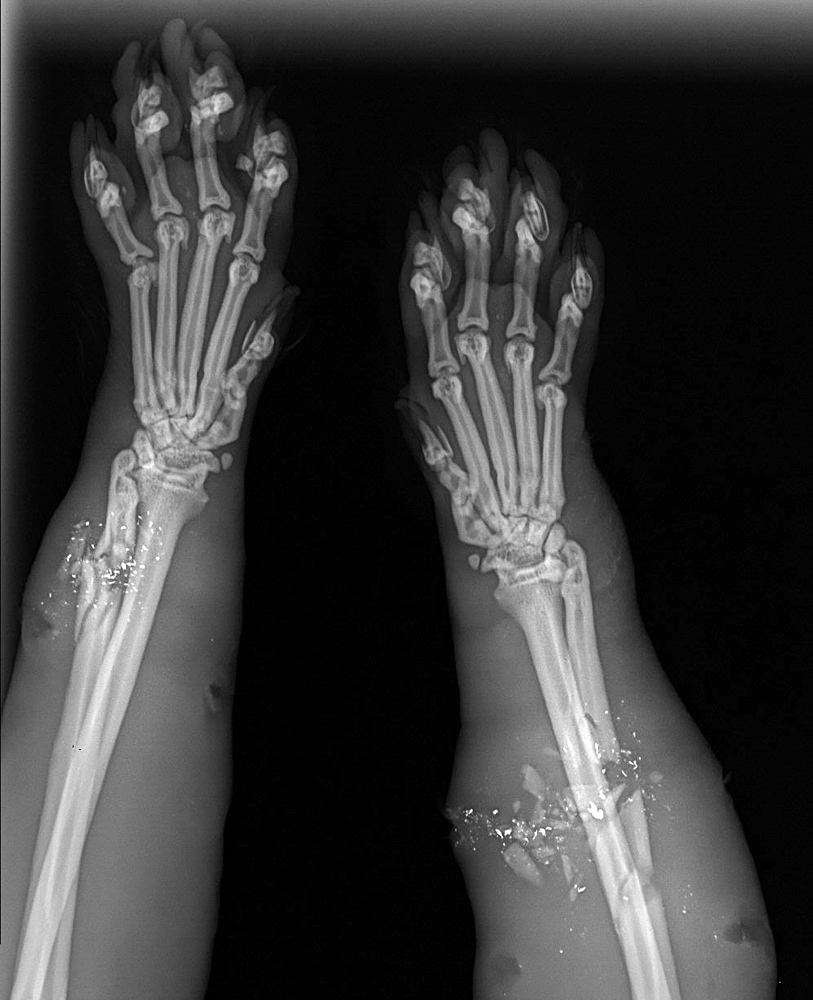

The Police Department is investigating the incident, while footing the medical bills for Clark, the former stray that is recovering in a Westbrook shelter from wounds that include shattered bones in both front legs.

Roth, from the animal shelter, said the injured cat was taken to an emergency veterinary hospital for initial treatment and is being monitored by an orthopedic surgeon. Now named Clark after Superman’s alter ego, Clark Kent, it is on strict cage rest while veterinarians wait to see if its bones will start healing without surgery. It’s unclear how much his medical care will cost the Police Department.